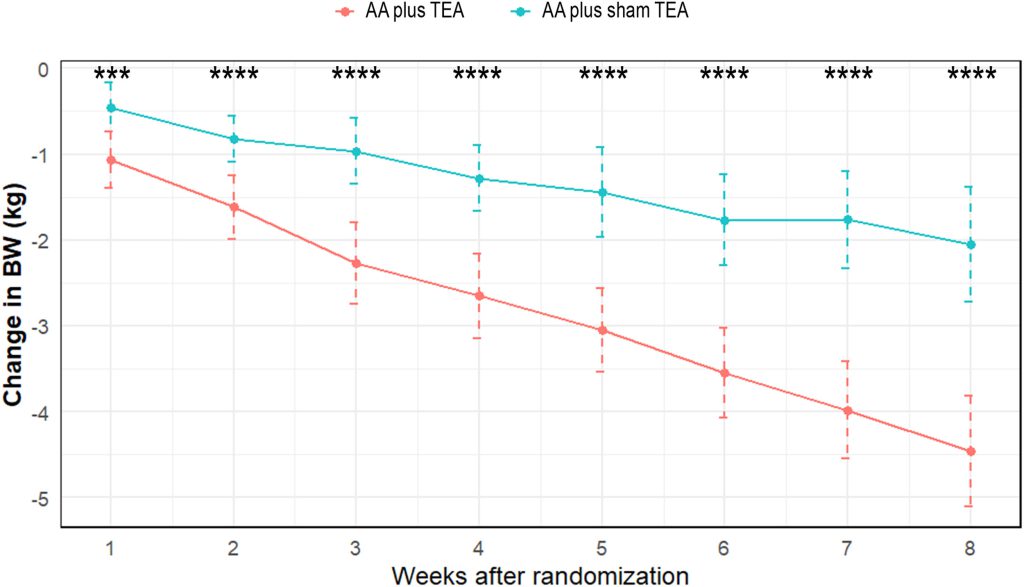

وزن بدن در هر دو گروه در طول دوره مداخله بهطور مداوم کاهش یافت. اگرچه پس از هشت هفته، تفاوت بین دو گروه معنادار نبود (ضمیمه ۳)، اما کاهش وزن در گروه AA + TEA از هفته اول بهطور معناداری بیشتر از گروه AA + TEA ساختگی مشاهده شد (شکل ۱).

پس از هشت هفته، در مقایسه با مقدار اولیه:

- در گروه AA + TEA میانگین کاهش وزن (SD) برابر با -۴.۴۵ (۱.۲۹) کیلوگرم بود.

- در گروه AA + TEA ساختگی این مقدار -۲.۰۵ (۱.۳۳) کیلوگرم بود.

- تفاوت میانگین (MD) بین دو گروه برابر ۲.۴۰ [۱.۷۵؛ ۳.۰۵] بود (جدول ۲).

*p < 0.001

**p < 0.0001 (مقایسه بین دو گروه با استفاده از آزمون تی دانشجویی). نقاط نشاندهنده میانگین و خطوط نشاندهنده انحراف معیار هستند.

- AA: طب سوزنی گوش | BW: وزن بدن | TEA: طب سوزنی کاشت نخ